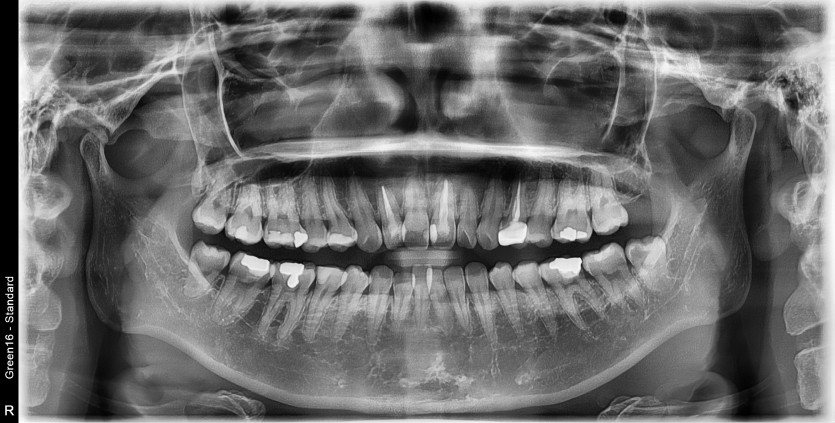

#38 사랑니 발치

구강 외과 전문의가 당일 발치했습니다.